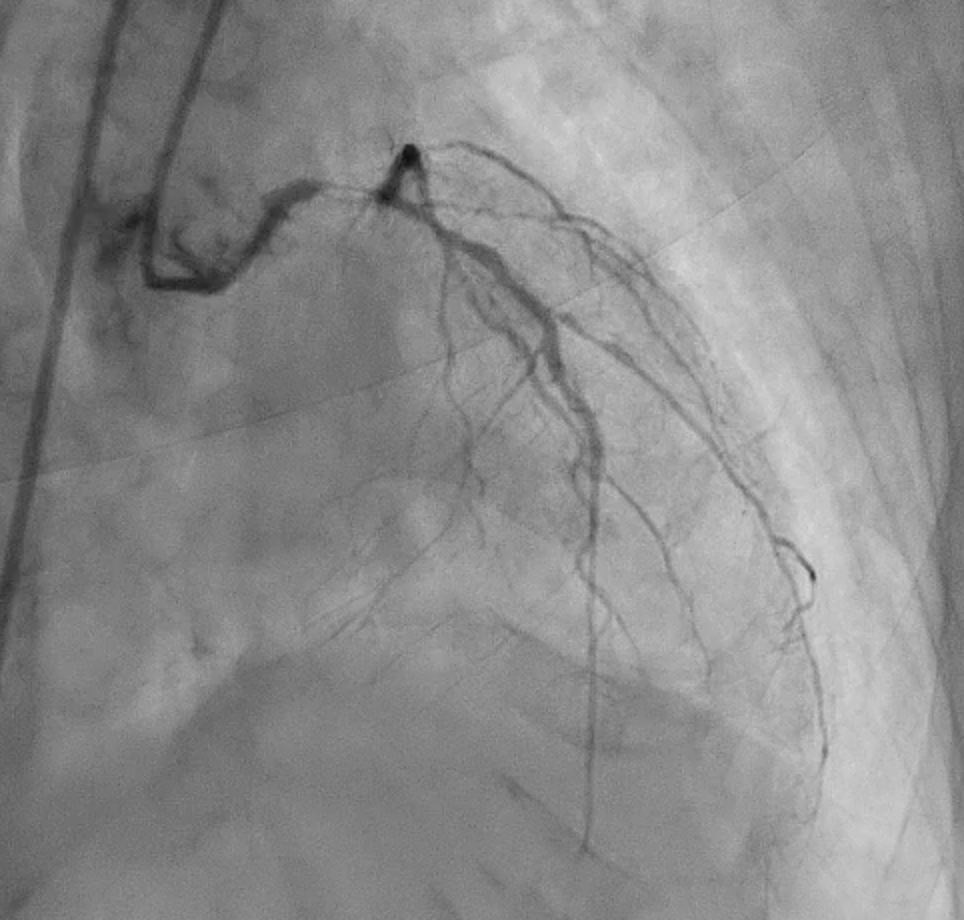

Severe CAD with LM + 3-vessel disease. dLM and shaft: critical stenosis; pLAD: critical stenosis; mLAD: s/p DES with stent underexpansion and proximal stent-edge restenosis; pLCX: s/p DES with proximal stent-edge restenosis; mRCA: 50% stenosis. SYNTAX score: 44.

Under IABP (left femoral), PCI via right brachial with 6 Fr EBU 3.5. Runthrough to LAD, Sion Blue to LCX. Predilation of LM/pLAD with 2.0¡¿20 mm balloon; IVUS pullbacks. Further dilatation with 2.5¡¿20 mm NC for mLAD underexpansion, pLAD, and LM. oLCX de novo and pLCX edge ISR predilated with 2.5¡¿20 mm NC; LCX ISR treated with DCB 2.5¡¿20 mm. Szabo technique attempted for LM–LAD with a 3.0¡¿24 mm DES; the undeployed stent dislodged during repositioning and was deployed at the dislodgement site. IVUS showed 2–3 struts protruding into the aorta from the LM ostium and incomplete pLAD coverage. Post-dilation with 3.5¡¿20 and 2.5¡¿20 mm NC; DCB 3.0¡¿20 mm for pLAD uncovered plaque and mLAD proximal edge ISR. Final CAG: TIMI 3 flow.At 3 months, staged PCI via right radial with 6 Fr EBU 3.5. Sion Blue ES to distal LAD. IVUS: mLAD stent underexpansion (MSA <2.0 mm©÷); wire not through struts. IVL 3.5¡¿12 mm initially could not cross LM; after guide exchange (JL 3.5, then EBU 3.0/3.5), IVL advanced to mLAD and delivered 100 shocks, producing a ring crack and area gain. Further dilation with 3.0¡¿20 and 3.5¡¿20 mm NC. IVUS: pLAD type B dissection without flow limitation. DCB 3.5¡¿40 mm to p–mLAD. LM ostial stent further dilated with 3.5¡¿20 mm. Final CAG: TIMI 3 flow.